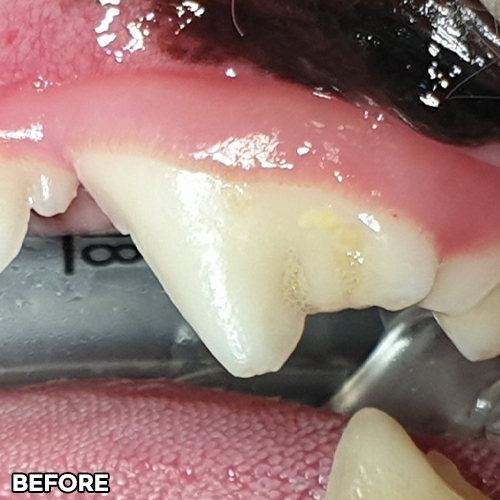

[구멍난 강아지 치아 레진치료 전후]